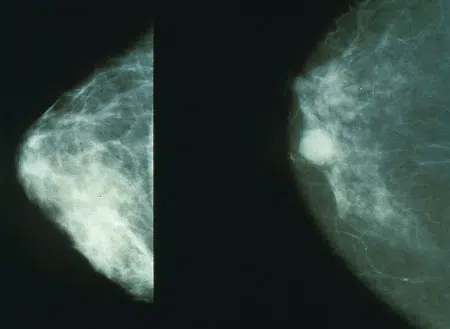

A mamografia é um exame por imagem que usa raios-X de baixa dosagem para analisar o tecido mamário. Crucial na detecção precoce do câncer da mama, ela permite identificar alterações como nódulos e microcalcificações antes de se tornarem palpáveis.

Limitações do exame: Mamografias podem ter limitações, especialmente em mulheres com mamas densas. Nesses casos, dificulta-se visualizar algumas lesões. Técnicas adicionais, como ultrassonografia, podem ser necessárias para avaliação completa.